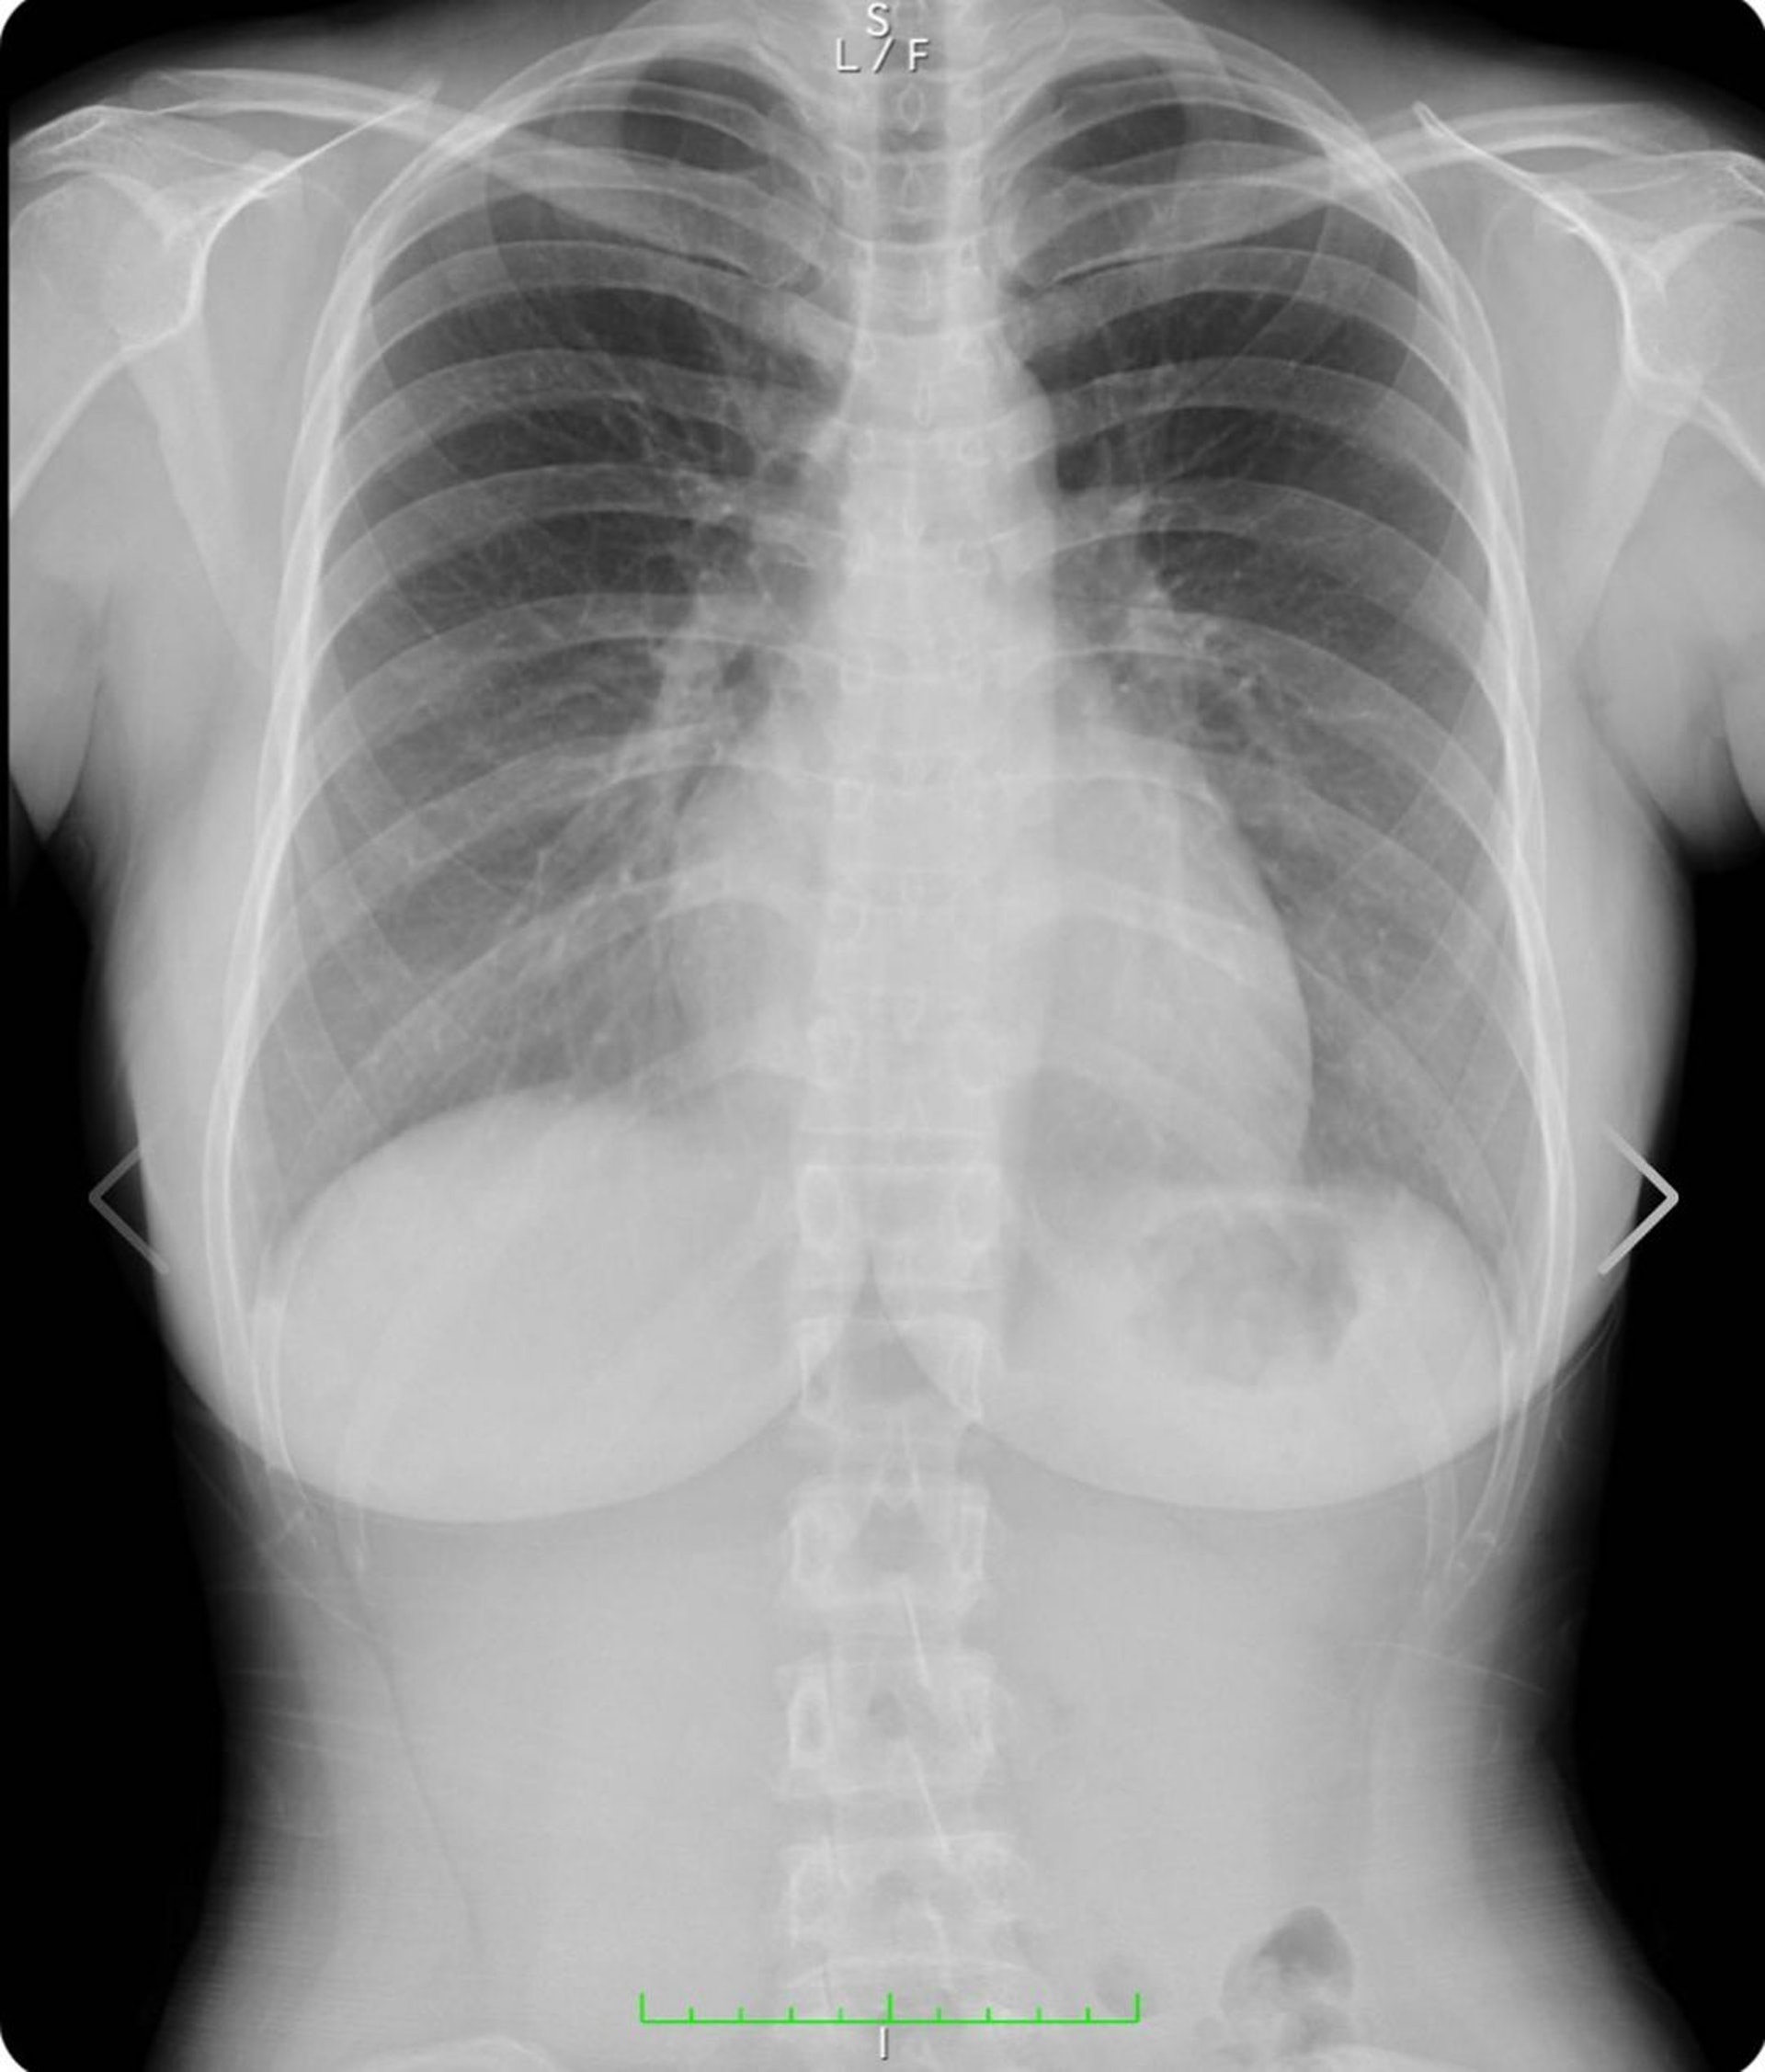

▲還有側面照